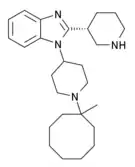

| Opioid peptides | Skeletal molecular images |

| Nociceptin |  |